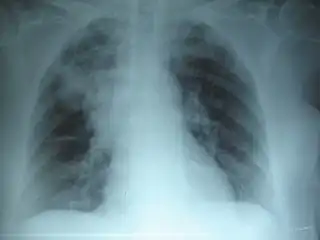

![]() Radiografía de tórax de una neumonía causada por influenza y Haemophilus influenzae, con consolidaciones parcheadas, principalmente en el lóbulo superior derecho (flecha). | ||